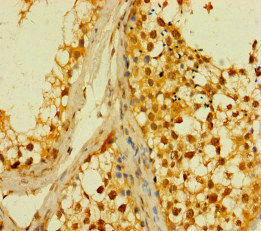

IHC image of CSB-PA836649LA01HU diluted at 1:200 and staining in paraffin-embedded human kidney tissue performed on a Leica BondTM system. After dewaxing and hydration, antigen retrieval was mediated by high pressure in a citrate buffer (pH 6.0). Section was blocked with 10% normal goat serum 30min at RT. Then primary antibody (1% BSA) was incubated at 4°C overnight. The primary is detected by a Goat anti-rabbit polymer IgG labeled by HRP and visualized using 0.05% DAB.